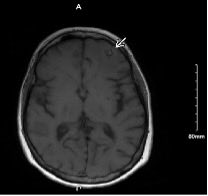

Neuroautopsy from a pt with disseminated coccidiomycosis. Prominent leptomeningeal inflammation with focal breakthrough into underlying parenchyma = meningoencephalitis. Beautiful yet scary spherules filled with endospores are clearly visible on H&E/LFB. #neuropath #forensicpath